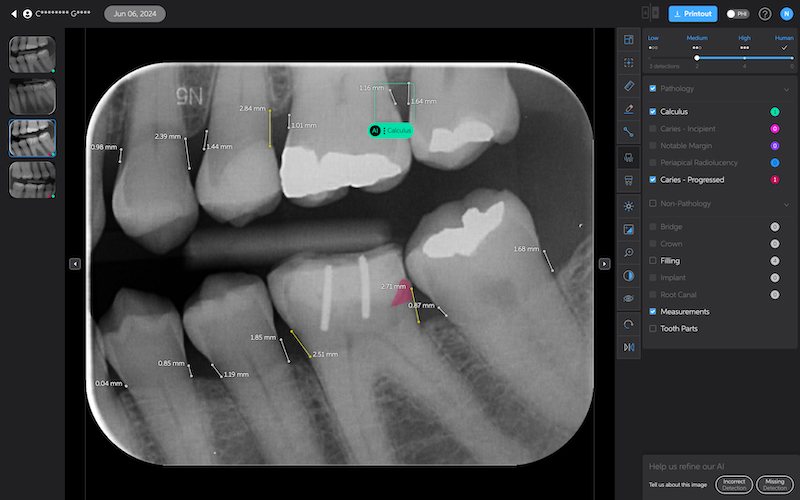

Bone Measurements

The system provides automated measurements from the crest of the bone to the cementoenamel junction (CEJ). These measurements are color-coded to indicate severity:

- White: 0-2.5 mm

- Yellow: 2.5-4 mm

- Amber: >4 mm

This feature is helpful for periodontal assessments, streamlining the process of identifying areas of bone loss. However, it's important to note that image angulation can affect the accuracy of these measurements, a limitation the system acknowledges.

I found these lines to be incredibly useful when describing patients' periodontal health. Cool feature, no doubt.

Calculus Detection

Green squares highlight areas of radiographic calculus. This tool is useful for hygienists and dentists in treatment planning and patient education.

Quite self-explanatory and the system didn't seem to miss often, if ever.

Caries Detection

The best for last and arguably the most well-thought-out feature. Especially with the tooth segmentation mode, which makes it easier for patients to understand their diagnosis and treatment plans.

The system uses two shades of pink to indicate potential caries:

- Light pink: Incipient caries (100% in enamel) - we will often review

- Darker magenta: Caries extending into dentin - we need to restore

The system even provides a percentage breakdown of enamel vs. dentin involvement. I have been blown away by its accuracy while using it, and it makes something that feels quite subjective (reading shades of grey) into a science.

This feature is very useful for patient education and deciding between preventive measures and restorative treatment. However, remember that radiographic evidence alone is not always sufficient for a definitive caries diagnosis.

Other features of Second Opinion

One of the strengths of Second Opinion's AI detection system is its flexibility. You can toggle different types of detections on and off, allowing for customized views depending on the focus of examination or patient education needs.